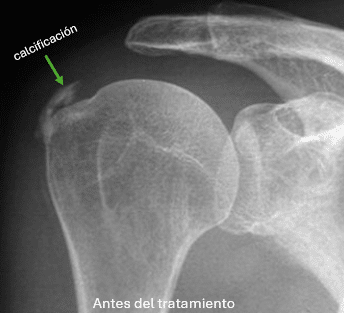

Las calcificaciones en el hombro son lesiones que aparecen con relativa frecuencia y generan mucho dolor y limitación, los tratamientos actuales van desde el uso de fármacos AINEs, la aplicación de frío/calor, fisioterapia e incluso infiltraciones, sin embargo un diagnóstico preciso es primordial para un tratamiento eficaz, en este sentido la ecografía es una técnica no tan solo que nos facilita el correcto diagnóstico, y localización, sino que a través de ella podemos tratar la calcificación en el hombro.

Las calcificaciones en el hombro se pueden clasificar ecográficamente según su forma (sólidas, pastosas, únicas, múltiples, fragmentadas…), según su tamaño (grandes o pequeñas), y según su localización (supraespinoso -80%-, infraespinoso -15%-, subescapular -5%-, bursales…)

En la unidad de dolor del Instituto Valenciano de Ozonoterapia (IVO3T) la técnica que suele usarse es la punción y aspiración del hombro, técnica también conocida como Barbotaje, o sea un lavado ecoguiado de las calcificaciones en el hombro, esto consiste en la colocación de una aguja bajo anestesia local en el centro de la calcificación, de tal forma que mediante la inyección a presión de suero salino o anestésico se rompa la calcificación y se vacíe el material cálcico a la jeringa utilizada para el lavado.